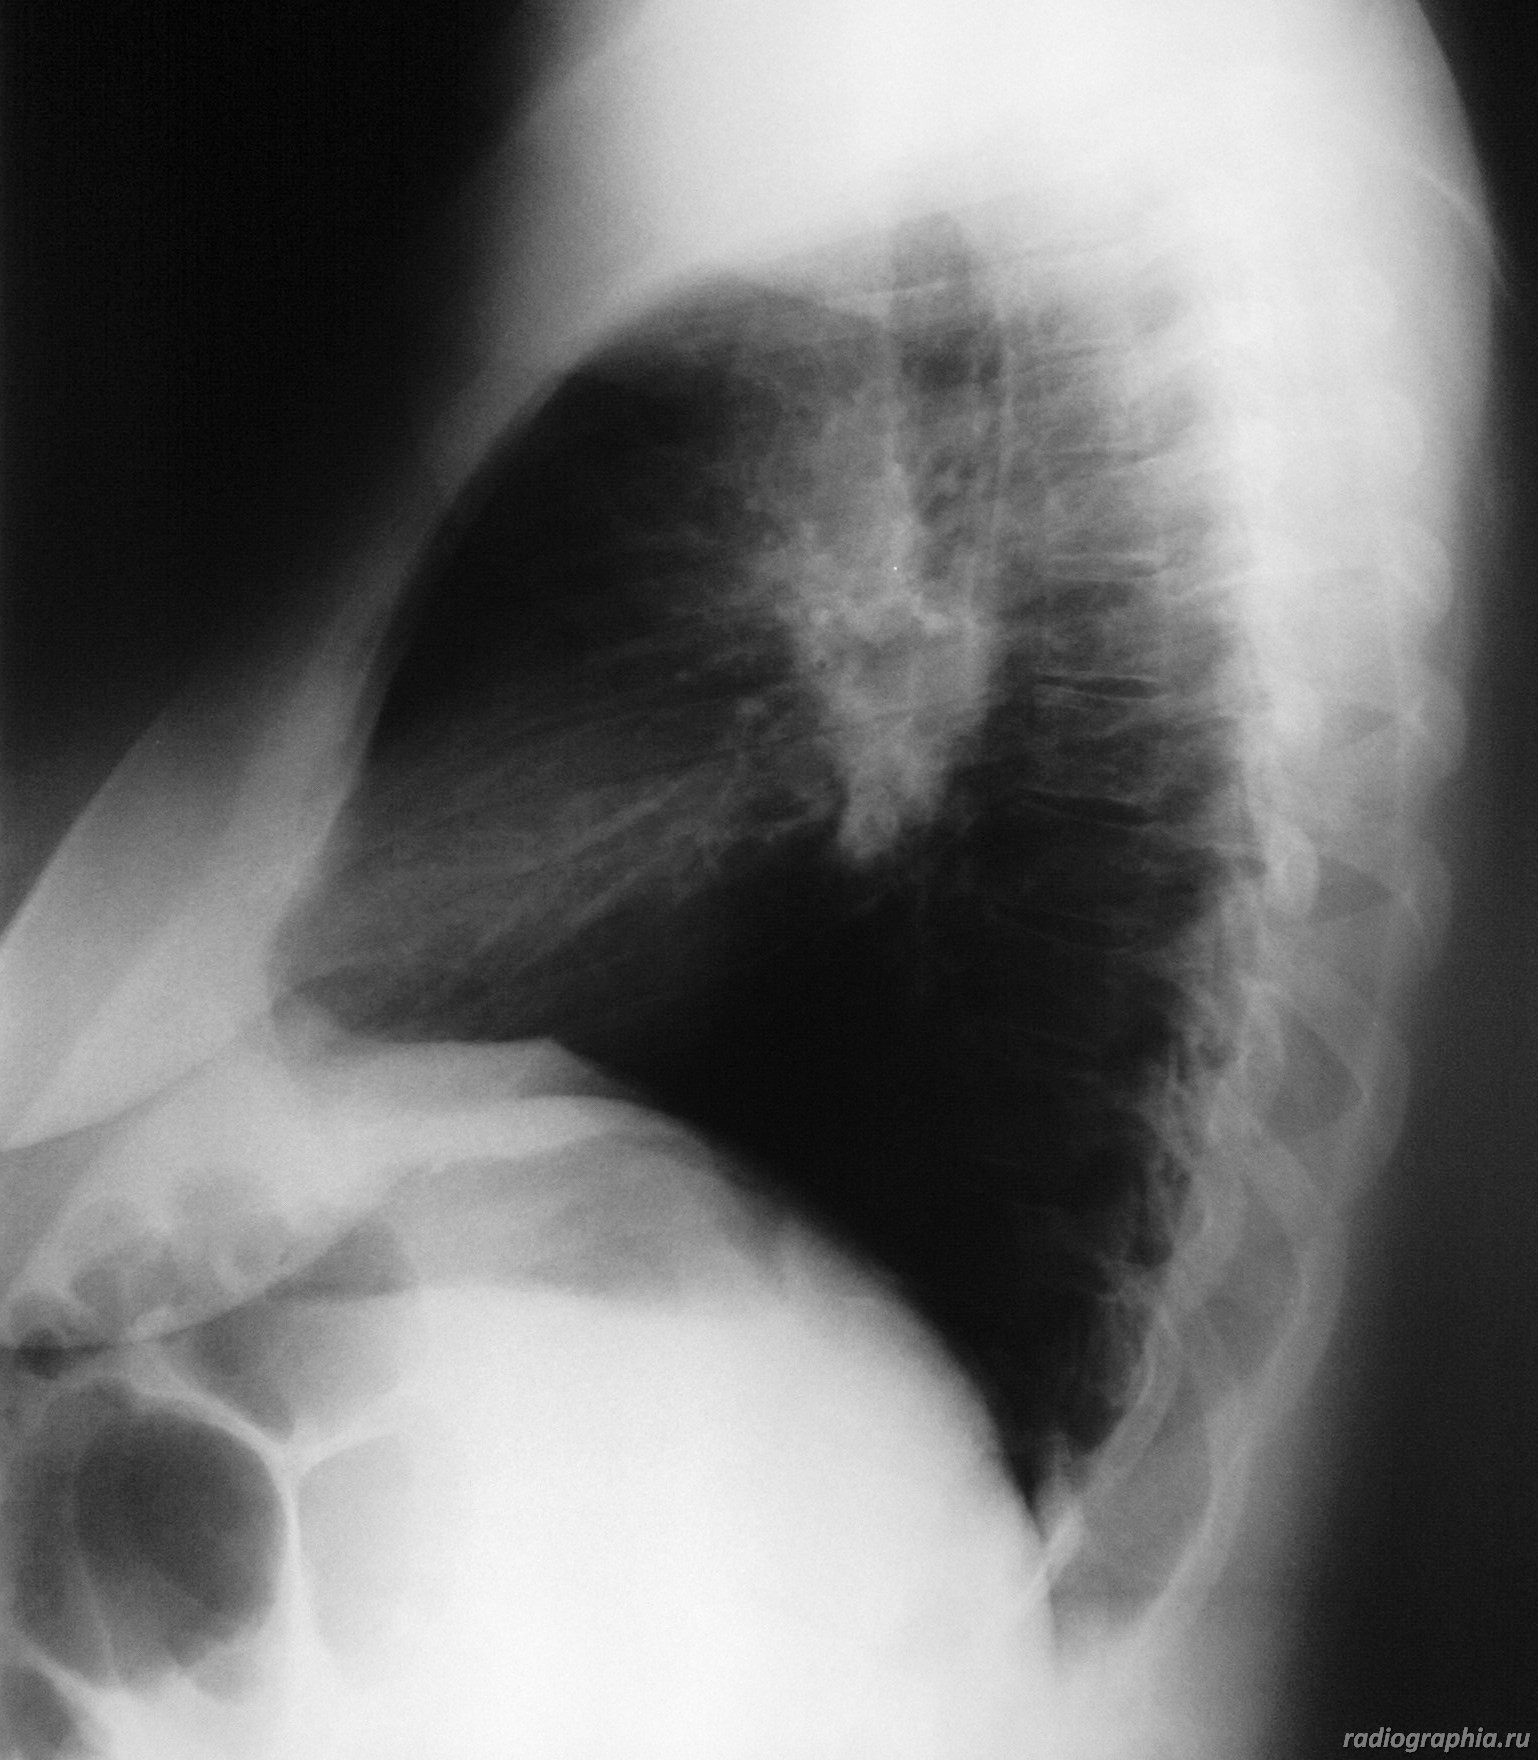

Рентгенография ОГК. Женщина средних лет.

интересует предыдущая рентгенодокументация (если есть :lol: ), анамнез заболевания. На момент осмотра больше данных за расширение легочных артерий , возможно начальные рентгенпризнаки развивающегося идиопатического легочного фиброза.Саркоидоз со стопроцентной уверенностью тоже исключать не стала бы.

Расширение верхнего средостения, широкие корни. У пациентки диагностирована лимфома. Была выполнена медиастиноскопия с забором лимфатических узлов на морфологию.